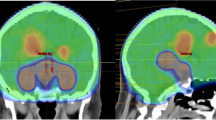

Pre-treatment gadolinium-enhanced T1-weighted magnetic resonance image (MRI) datasets of 865 patients with brain metastases from the years 2014–2018 were reviewed at the University of Luebeck, Germany. The HT-P area was contoured on axial planes for each patient as described previously by others [20, 21]. In short, minimal requirements for sufficient contouring and delineation were as following: CT images (axial planes) were fused to images obtained via T1-weighted MRI images (gadolinium contrast enhanced) acquired on 1.5 T resonance scans with a slice thickness of 1.5 mm. The hypothalamus and pituitary gland (including the pituitary stalk) were contoured on T1-weighted axial MRI sequences and a margin of 5 mm was added (see Fig. 1) [20, 21].